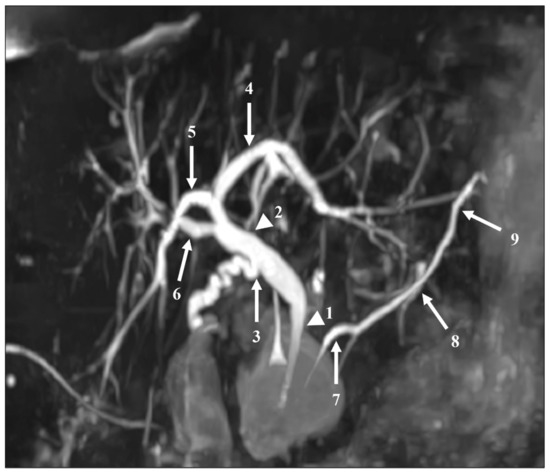

Based on the consensus between the two readers, CBD lithiasis was present in 10 of the 54 patients. In three patients, the calculi were visible on both MRCP sequences and on a non-MRCP sequence and confirmed by ERCP. In five patients, CBD lithiasis was visible on the RT-MRCP sequence and on a non-MRCP sequence but not on the CS-BH-MRCP sequence. Among these five patients, only one had calculi visible by ERCP and three had uninterpretable CS-BH-MRCP images (diagnostic confidence of 1). Finally, in two patients, calculi were visible on the CS-BH-MRCP sequence and on non-MRCP sequences but not on the RT-MRCP sequence. Among these two patients, only one had calculi visible by ERCP. The RT-MRCP was considered interpretable in both patients. No significant difference was found between the CS-BH-MRCT and RT-MRCP sequences for the detection of bile-duct lithiasis (p = 0.30). One stone was fortuitously discovered in one patient referred for BD-IPMN, only on CS-BH-MRCP sequence (not included in analysis). Figure 4 shows three examples of MRCP images of patients referred for suspected choledocholithiasis using RT-MRCP and CS-BH-MRCP sequences. Appendix A, Table A6 shows the number of CBD lithiasis detection based on the consensus between the two readers with each MRCP sequence and the agreement between the two sequences.

Figure 4. Three examples of MRCP images of patients referred for suspected choledocholithiasis using RT-MRCP and CS-BH-MRCP sequences. (a,b) MRCP images from a 41-year-old female. The stone within the common bile duct (arrow) was clearly seen with both RT-MRCP (a) and CS-BH-MRCP (b) sequences with a diagnostic confidence score of 3. RT-MRCP acquisition time was 4 min 30 s. (c,d) MRCP images from a 61-year-old female. Both RT-MRCP (c) and CS-BH-MRCP (d) sequences showed intra-hepatic bile duct dilation upstream of calculi (arrows) in the common bile duct with a diagnostic confidence score of 3. RT-MRCP acquisition time was 3 min 23 s. (e,f) MRCP images from a 55-year-old male. (e) RT-MRCP showed very poor image quality and was uninterpretable. The diagnostic confidence was scored 1. (f) CS-BH-MRCP showed better image quality, with a diagnostic confidence score of 2, allowing moderate confidence to diagnose the absence of CBD lithiasis. RT-MRCP acquisition time was 14 min 41 s.